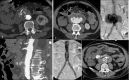

Objectives: To demonstrate the various presentations of acute aortic pathology and to present diagnostic and therapeutic approaches.

Methods: Diagnostic imaging is the key to the reliable diagnosis of acute aortic pathology with multi-slice computed tomography angiography (CTA) as the fastest and most robust modality. Endovascular aortic repair (EVAR) with stent grafts and open surgical repair are therapeutic approaches for aortic pathology.

Results: CTA is reliable in diagnosing and grading aortic trauma, measuring aortic diameter in aortic aneurysms and detecting vascular wall pathology in acute aortic syndrome and aortic inflammation. CTA enables planning the optimal therapeutic approach. Stent graft implantation and/or an open surgical approach can address vascular wall pathology and exclude aortic aneurysms.

Conclusion: Aortic emergencies have to be detected quickly. CTA is the imaging method of choice and helps to decide whether elective, urgent or emergent treatment is necessary with EVAR and open surgical repair as the main treatment approaches.

Teaching points: • To present aortic pathology caused by trauma • To present acute aortic syndrome (aortic dissection, intramural haematoma and penetrating ulcers) • To present symptomatic and ruptured aortic aneurysm • To present infection (mycotic aneurysms/aorto-duodenal fistulae) or iatrogenic injury of the aorta • To understand different presentations for treatment planning (EVAR and open surgery).